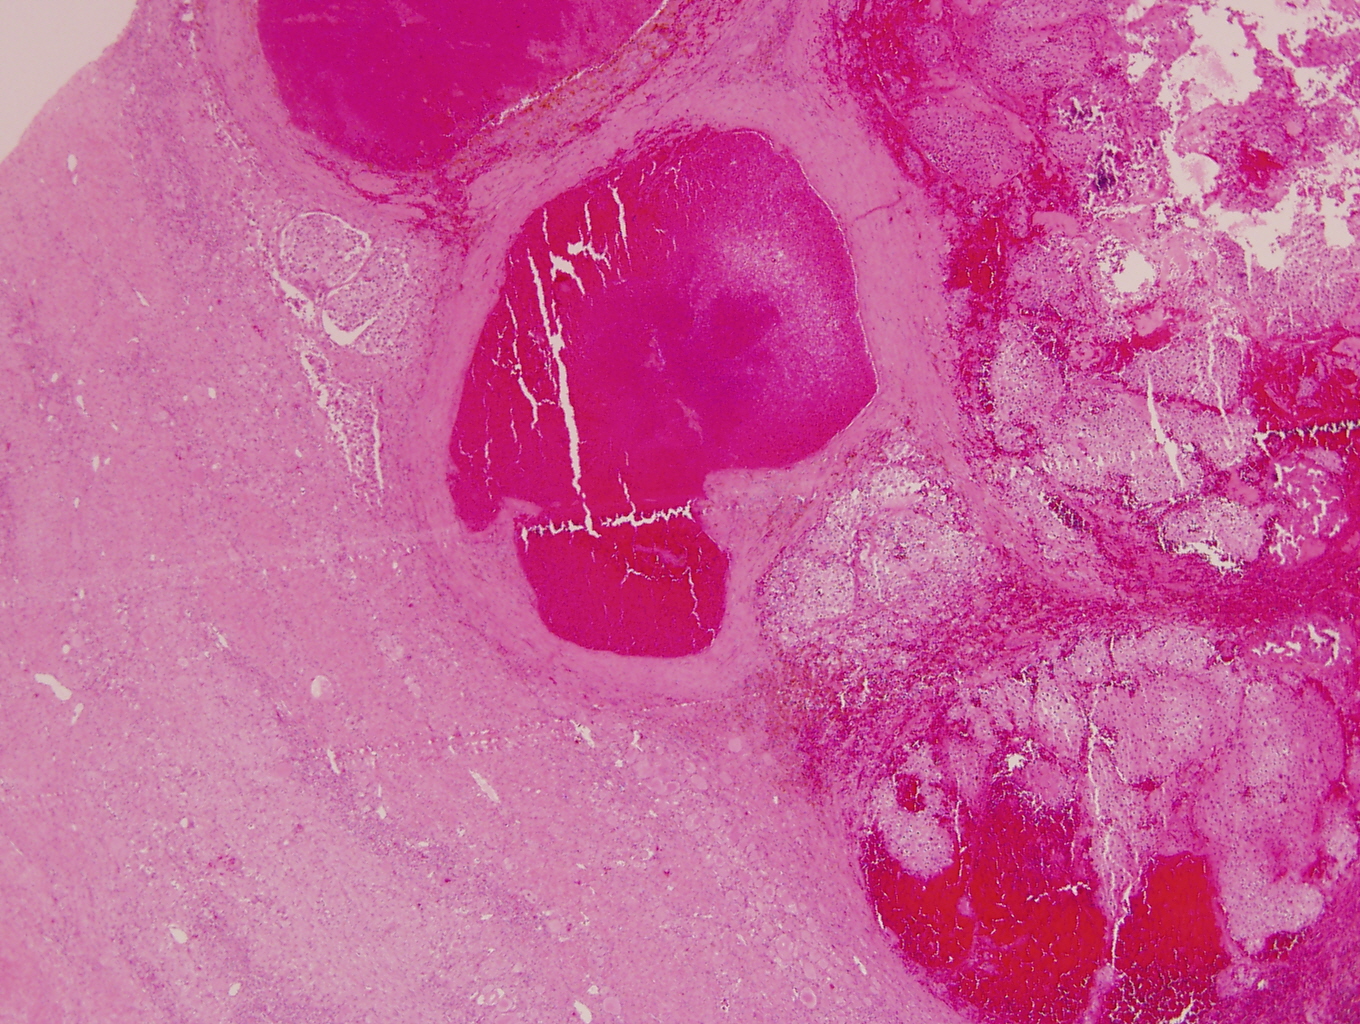

- More homogeneous and mature appearance than neuroblastoma

- Varies by subtype, from circumscribed ovoid mass to large multilobulated tumor

- Stroma rich, nodular subtype: area(s) of stroma poor, immature tumor are usually hemorrhagic with well defined borders (J Natl Cancer Inst 1984;73:405)

- Calcification (chalky white, yellow areas) and cystic degeneration may occur

- If large, adrenal gland may be difficult to identify

Intermixed type

Nodular type